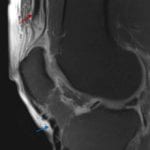

- Avulsion fracture from the superior patellar pole at the quadriceps tendon insertion with associated patella baja

- Multiple small avulsed bone fragments, superiorly distracted up to 10 mm, with the largest avulsed fracture fragment measuring 10 mm

- Moderate joint effusion

- Quadriceps tendon avulsion fracture

Acute quadriceps avulsion fractures with multiple superiorly distracted bone fragments and associated patella baja.

Moderate-sized joint effusion.